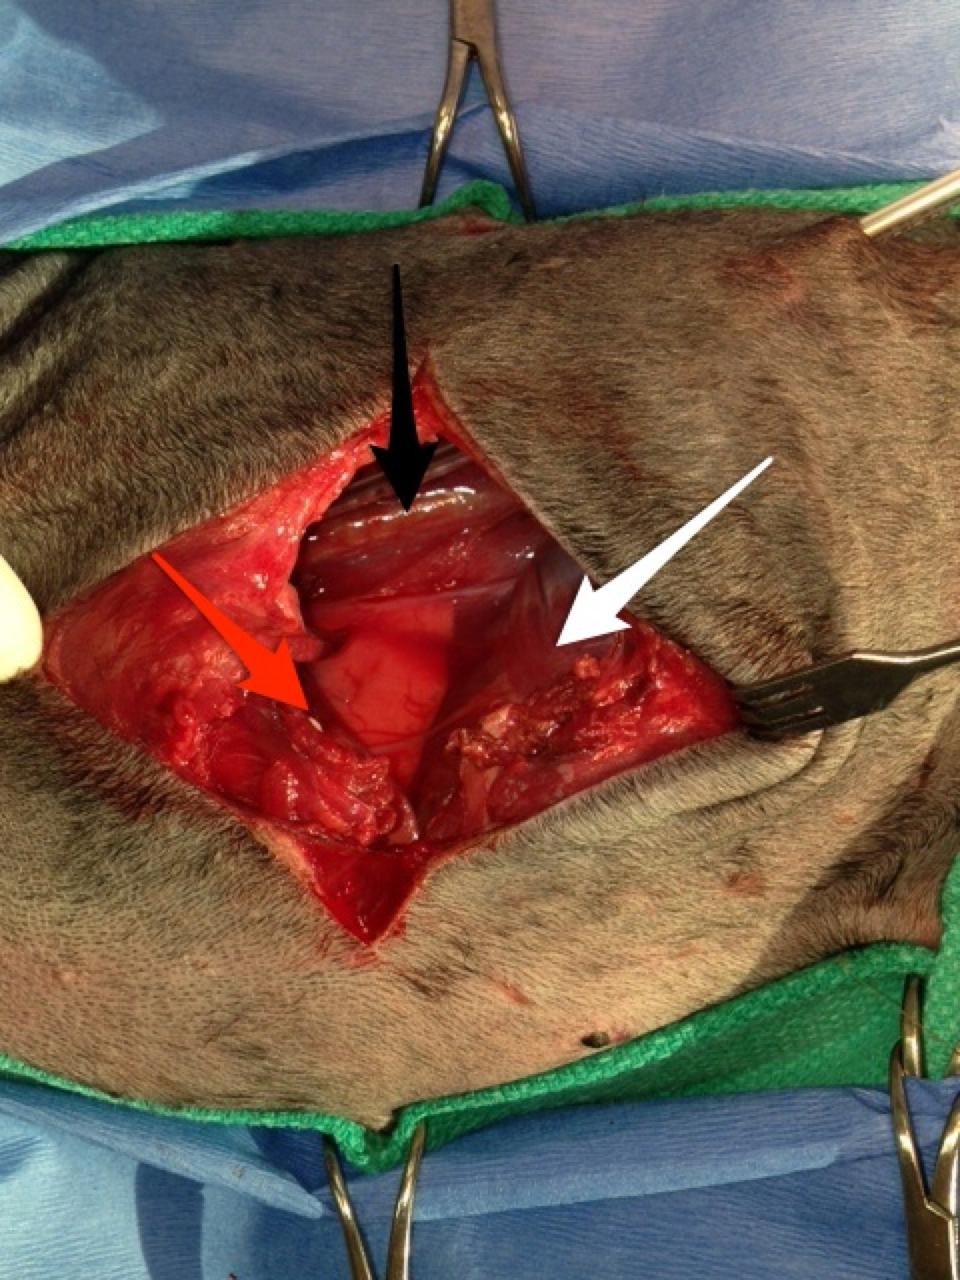

Smokey was stabilized by the emergency service and prepared for surgery once transferred in the morning. Based on the injuries, Smokey had a thoracic exploratory to evaluate the thoracic wall wounds and subsequent internal injuries. Surgery revealed a large thoracic wall defect and multiple fragmented ribs, some of which needed to be removed. Interestingly, the left caudal (posterior) lung lobe had a large laceration caused by one of the rib fragments, necessitating removal of the lung lobe. The remaining thoracic wall defect was too large to close primarily.

The white arrow denotes the diaphragm, the red arrow is showing the muscle of the thoracic wall and the caudal edge of the heart and the black arrow denotes the great vessels (caudal vena cava and caudal aorta).